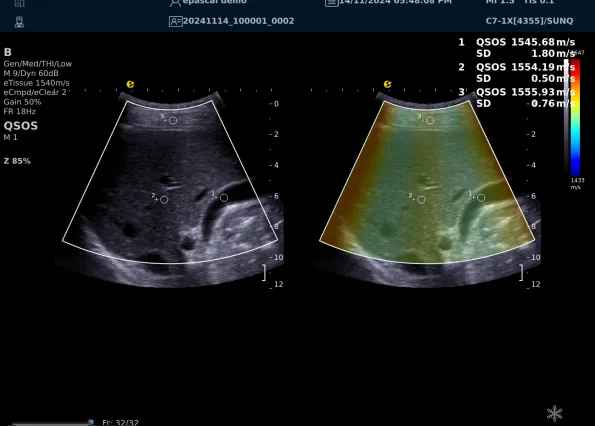

640.jpg123 (2).jpg可以设想,单位时间可发射的脉冲波越多、单位面积可发射的脉冲波越密集,得到的数据结果就越快、越多。也就是说,如果医生希望得到实时、大幅的声速定量图像,就需要超声系统具备“超快速”发射和接收的能力,百乐博平台医疗(ESI)ePascal东风系列超声平台的200+倍成像速度,成为了这项新技术得以临床应用的重要条件。

以上为应用声速定量成像技术检查肝脏的超声图像,图中在取样框内选择了三个测量区域,得出了各区域内的组织声速值以及声速衰减系数等结果。